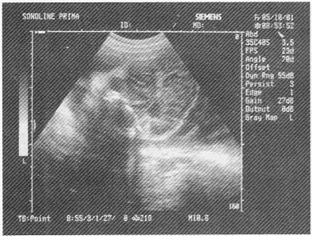

3.如圖,女性,25歲,無明顯自覺癥狀,盆腔橫斷面,最可能的診斷是

A.附件區炎性包塊

B.異位妊娠

C.畸胎瘤

D.黃體囊腫

E.正常聲像圖

正確答案:C解題思路:附件區見無回聲暗區,邊界清晰,其內見強回聲水平分界線,在線上方為脂質成分,呈均勻密集細小光點,水平線下方為無回聲暗區。